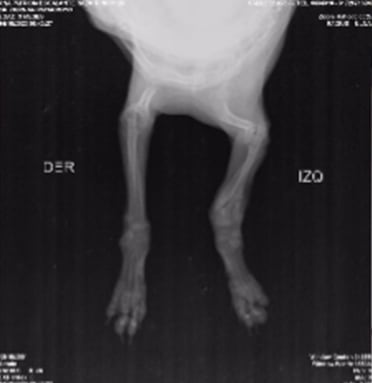

De acuerdo con Alejandra Prada, activista por los derechos de los animales en la capital santandereana, la perra habría sido arrojada desde un segundo piso y, tras el fuerte golpe, sufrió varias fracturas en sus paticas que le impiden moverse con normalidad.

“Sol es una pequeña bebé de tres meses que tiraron por un balcón y la abandonaron a su suerte.Las personas se fueron de la casa y la dejaron ahí solita y llorando. El golpe ocasionó que su patita esté totalmente partida, es una fractura que tiene muchas semanas, se imaginan el dolor y su sufrimiento”, dijo Alejandra Prada.

Ante la gravedad de la lesión, la perrita fue sometida a una cirugía. Sin embargo, el procedimiento aún no ha sido terminado en su totalidad y por ello, Alejandra hace un llamado a la comunidad para poder costear todos los gastos que implica el proceso de recuperación de la canina.

“Sol es una perrita demasiado noble y tierna, bajo mi cuidado estará bien y la sacaremos adelante. Quiero contarles que está en recuperación, controles y posteriores terapias para la movilidad total de su patita”, agregó Prada.